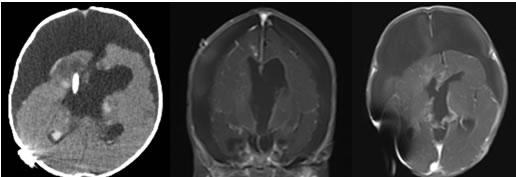

出生50天,全麻下行右侧脑室-腹腔分流术,分流管压力设置为14cmH2O。术后囟门张力下降,精神状态好转。

术后复查CT结果:分流管位置佳,肿瘤体积较5天前明显增大。